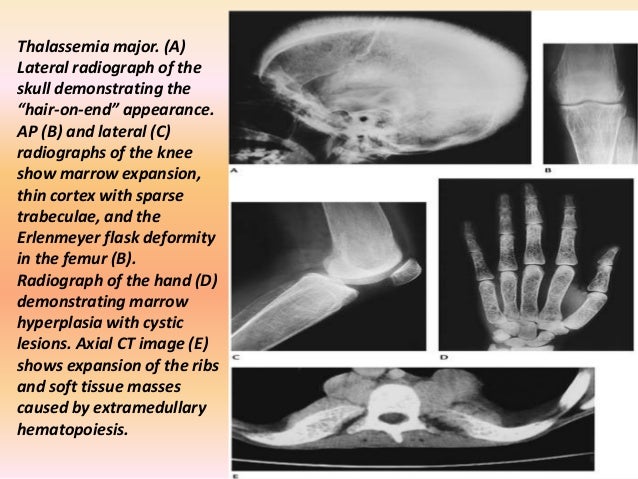

Get Oral Manifestations Sickle Cell Anemia Dental Radiograph Pictures. Nevertheless none of them have showed epidemiological data for a. The diploic space is markedly widened due to marrow hyperplasia.